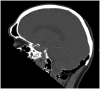

Hyperpneumatization is a rare pathological process where air-filled cavitation form within solid bone architecture occurring at sites where physiological pneumatization is not seen. Extension of this process into the atlanto-occipital region is considered extremely rare and is only quoted several times in the literature. In this case report, we present a 66-year-old man who presented with an 8-month history of a worsening frontal headache and blocked sensation in his left ear. Subsequent CT head evaluation revealed hyperpneumatization affecting C1 vertebra, temporal and occipital bones with extension into the clivus. A rare complication of epidural emphysema was seen. The aetiology of hyperpneumatization is uncertain, although it is thought to be either congenital or acquired. In our case, clinical suggestion of eustachian tube dysfunction and radiological findings of thickened sinus mucosa and a unilateral nasal polyp point to chronic recurrent coryzal illnesses, which may indicate an acquired mechanism. Management is mostly conservative with surgical management reserved for high risk or refractory cases.